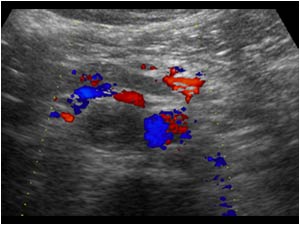

Huyết khối TM chủ dưới

Huyết khối TM chủ dưới - Ảnh 3

» Thông tin: Nữ giới – 68 tuổi.

» Lâm sàng: Sưng phù chi dưới.